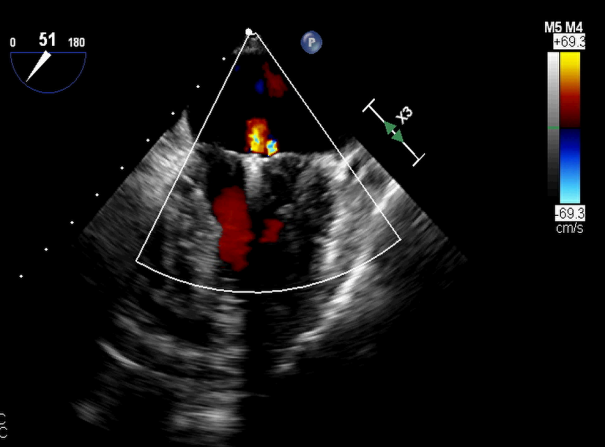

患者术前TEE提示重度功能性二尖瓣反流,反流位于A2/P2,瓣膜活动度可,后瓣较短,手术难度较高(图1)。手术采用经典股静脉房间隔途径,房间隔穿刺后植入24F导引导管及二尖瓣夹输送系统,在TEE引导下准确植入一枚二尖瓣夹,瓣膜夹位置稳定。瓣膜夹植入后反流明显减轻至轻度(图2),二尖瓣跨瓣平均压力阶差2mmHg,双孔化形成,遂移除输送系统。

图2:植入一枚瓣膜夹之后二尖瓣反流明显减轻